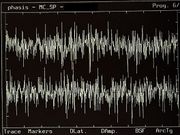

| 13:53, 5 February 2023 | Bruxer SP2.jpg (file) |  |

780 KB | 1 | |